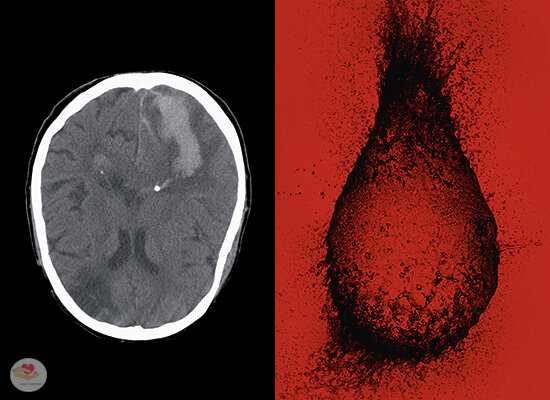

Инсульт. Почему высокое давление может разрушить ваш мозг?

Под притоком крови место появившейся бляшки отрывается от места крепления вашей артерии и с кровотоком устремляется в мозг, где застревает в каком-нибудь узком сосуде, тем самым его перекрывая. Как следствие, кислород не попадает в клетки головного мозга, которые расположены дальше по направлению движения крови. Это явление — ишемический инсульт.

5. Разрушаются мозговые клетки

Без притока кислорода мозговые клетки погибают в течение пары минут. Это зависит о того, в какой части мозга случилась проблема и о количества пострадавших клеток. В следствии всего этого дела, возможно как головокружение, так и пространственная дезориентация и сильнейшая головная боль, вплоть до серьезных заболеваний.